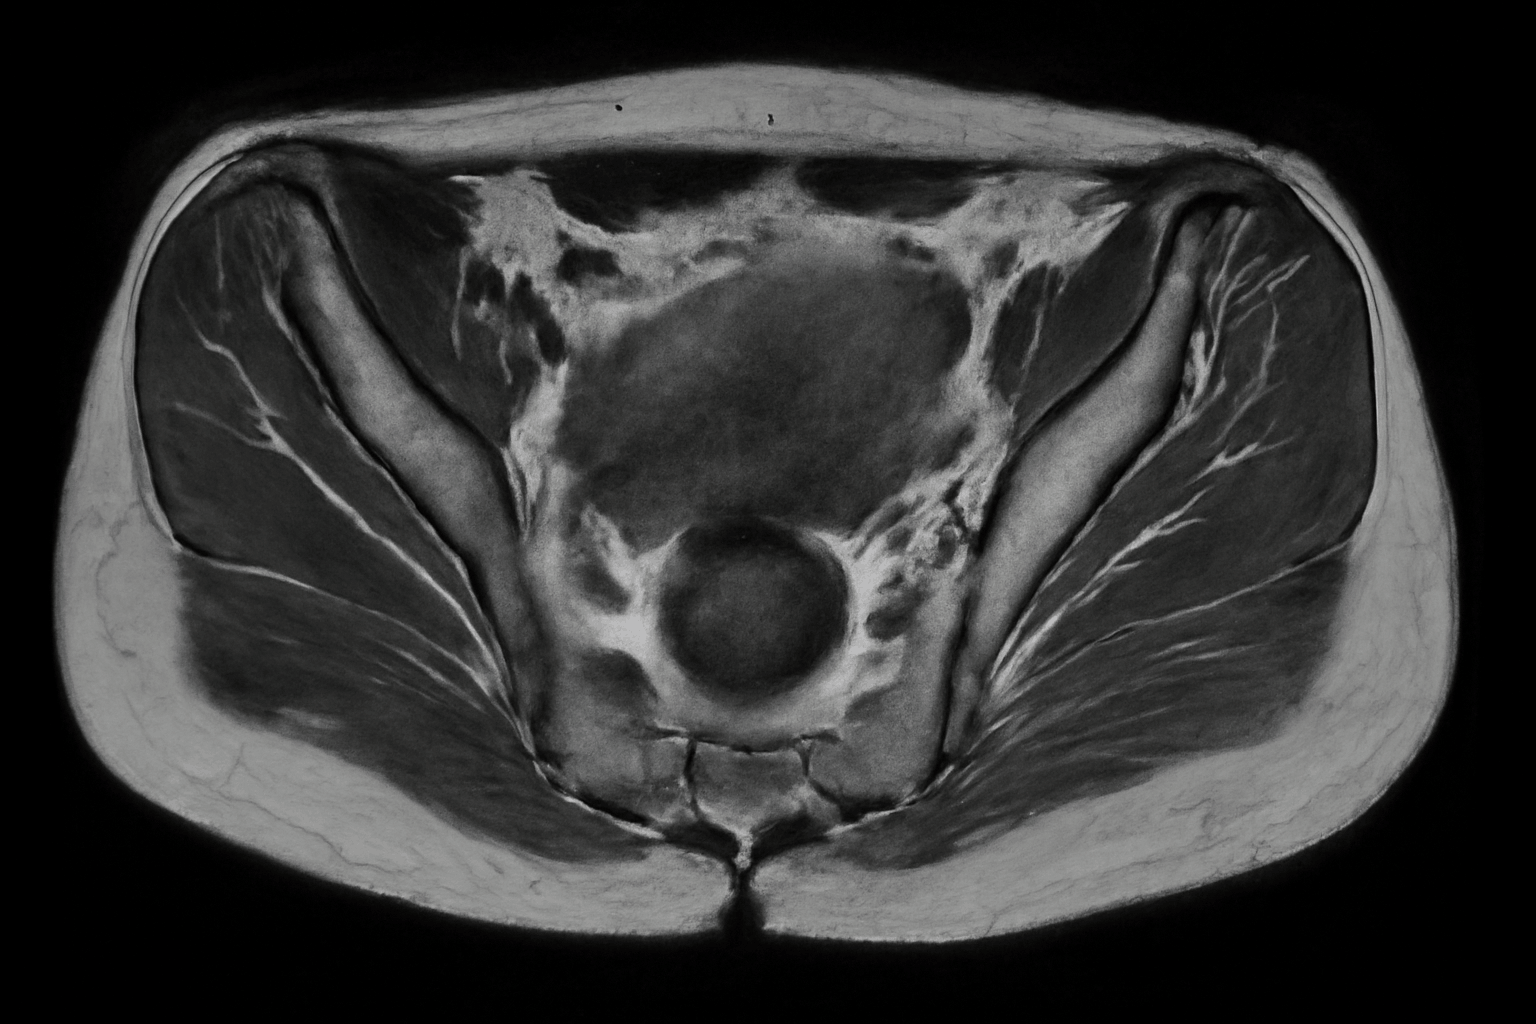

Магнитно – резонансная томография тазобедренного сустава является важной диагностической процедурой, позволяющей оценить состояние суставов и окружающих тканей. Этот метод обеспечивает высокую точность изображения, что помогает врачам в постановке правильного диагноза. Своевременное обращение к специалистам и прохождение исследования может предотвратить осложнения и улучшить качество жизни пациентов.

МРТ тазобедренного сустава в Зеленограде отличается высокой точностью и безопасностью. Процедура проходит на современном оборудовании, что позволяет получать детализированные изображения суставов.

Томография тазобедренного сустава является эффективным методом диагностики и может выявить следующие проблемы:

- Травмы, переломы, разрывы связок и повреждения мягких тканей.

- Воспалительные заболевания: артриты и бурситы, а также другие воспалительные процессы.

- Дегенеративные изменения: остеоартрит.

- Опухолевые процессы: новообразования в области сустава или окружающих тканей.

- Асептический некроз: умерщвление костной ткани, вызванное нарушением кровоснабжения.

Эти данные помогают врачам установить точный диагноз и выбрать наиболее подходящее лечение для пациента.